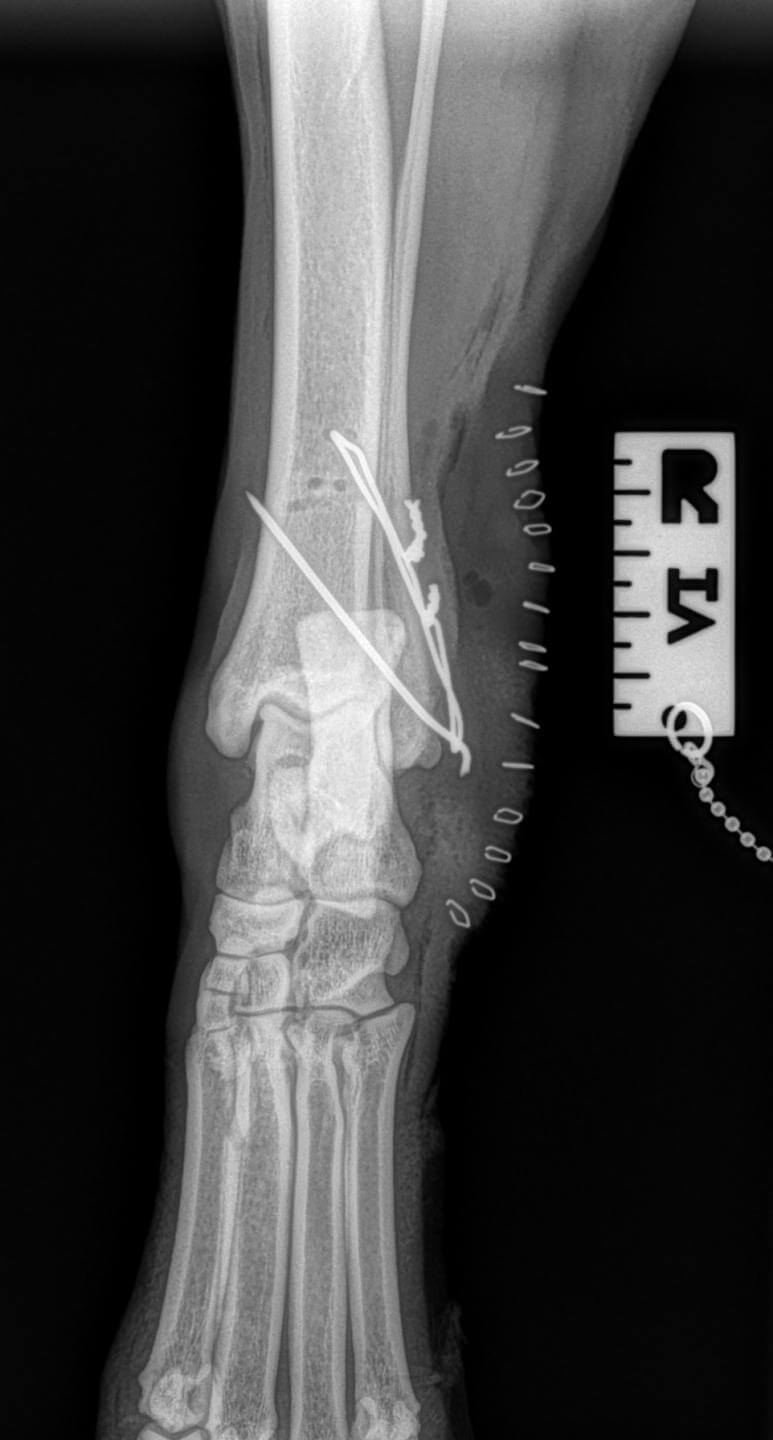

Tibia/Fibula

Lateral Malleolus Fracture